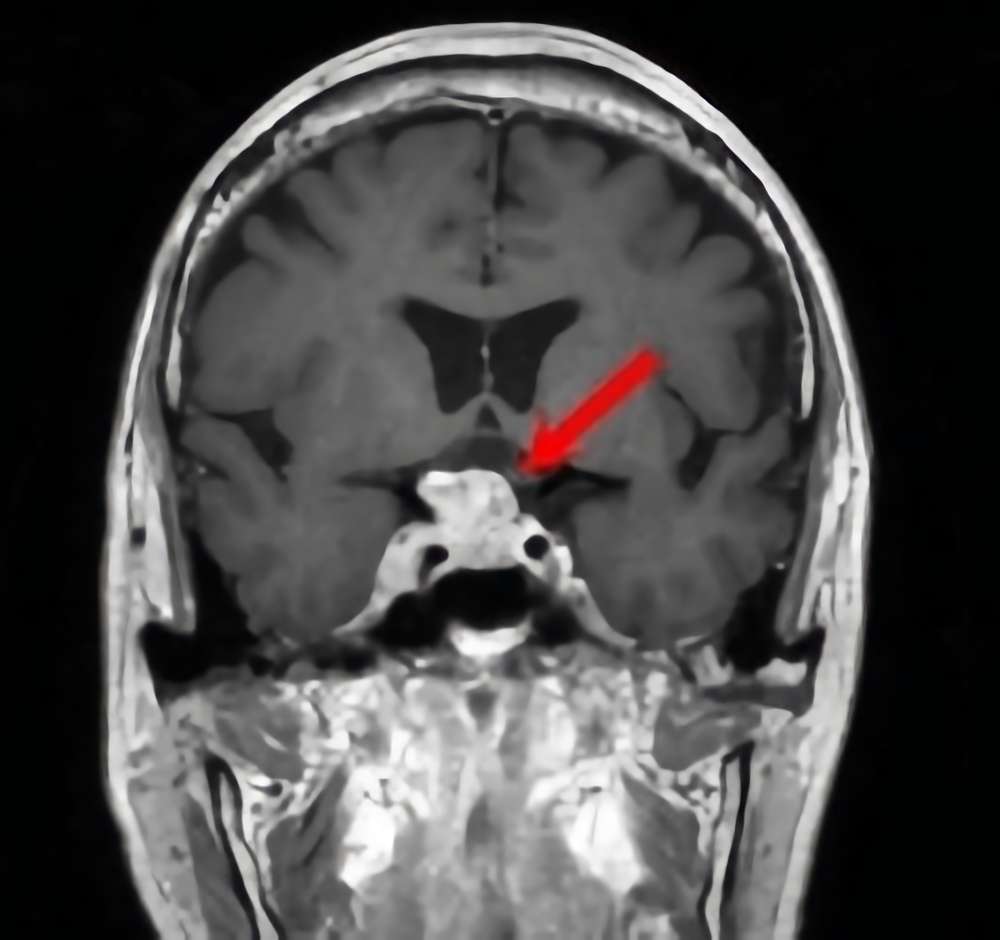

※ 画像をクリックすると拡大表示します。症例No.は平成29年から起算しています。

11

’17_11

'17年1月

50代

病名

術式

備考

下垂体腺腫

経鼻的腫瘍摘出術

断層撮影

手術前

1

手術前2

手術後